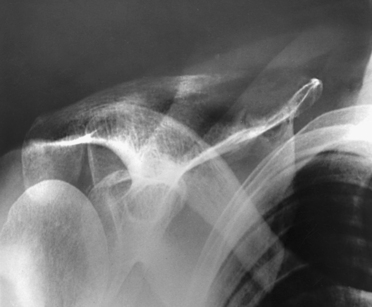

• Anterior dislocation of the humeral head can result in a wedge-shaped compression fracture of the articular surface of the humeral head, called the Hill-Sachs defect.1 The fracture is located on the posterolateral humeral head. An exaggerated external rotation of the arm may be required to see the defect.

Structures shown: An inferosuperior axial image shows the proximal humerus, the scapulohumeral joint, the lateral portion of the coracoid process, and the AC articulation. The insertion site of the subscapular tendon on the lesser tubercle of the humerus and the point of insertion of the teres minor tendon on the greater tubercle of the humerus are also shown. A Hill-Sachs compression fracture on the posterolateral humeral head may be seen using the Rafert modification (Figs. 5-29 and 5-30).

Fig. 5-29 A, Inferosuperior axial shoulder joint: Lawrence method. B, Inferosuperior axial shoulder joint: Rafert modification showing Hill-Sachs defect (arrow). C, Coronal MRI of shoulder joint showing Hill-Sachs defect (arrow) after recurring shoulder dislocation. (A and B, From Rafert JA et al: Axillary shoulder with exaggerated rotation: the Hill-Sachs defect, Radiol Technol 62:18, 1990. C, From Jackson SA, Thomas RM: Cross-sectional imaging made easy, New York, 2004, Churchill Livingstone.)